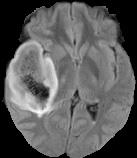

We conducted experiments on four brain imaging datasets: BraTS2017, BraTS2018, BraTS2019, and ISLES2022 [33, 34, 35, 36]. The BraTS datasets, developed for the MICCAI brain tumor segmentation challenge, contain 285, 285, and 335 labeled cases respectively, categorized into high-grade and low-grade gliomas. Each case includes 3D MRI scans from four modalities (T1, T2, FLAIR, T1c); we primarily used FLAIR. Preprocessing involved brain region cropping and intensity normalization. Dataset splits were 200/25/60 as train/val/test for BraTS2017 and BraTS2018, and 250/25/60 for BraTS2019. All experiments were conducted independently with models trained from scratch.

ISLES2022 focuses on stroke lesion segmentation in 3D multimodal MRI, with 250 cases including DWI, ADC, and FLAIR. We used DWI and split the dataset into 150 training, 40 validation, and 60 testing samples.

Quantitative Results. Tables 3–4 report results on BraTS2019, BraTS-2018, BraTS2017, and ISLES2022 datasets with limited labeled data (4% or 10%). On BraTS2019, our method outperformed most competitors in Dice, Jaccard, and 95HD, with a notable lead under the 4% setting, despite slightly lower ASD. On BraTS2018, it consistently surpassed all baselines, achieving nearly 2% higher Dice than the runner-up. It also achieved top performance on all metrics for BraTS2017, highlighting strong robustness and generalization. For ISLES2022 with 10% labeled data, our method significantly outperformed DAE-MT and closely matched the fully supervised model.

Qualitative Results. Figures 4, 3 present visual comparisons of the predicted segmentation results from our method and other baselines on the middle slice of the BraTS2018, BraTS2019, and ISLES2022 datasets. Our method demonstrates greater robustness and better coverage of the ground truth regions, particularly in areas where other methods fail to identify lesions and incorrectly classify them as background. Furthermore, our approach yields more accurate boundaries and preserves the overall shape of the target structures more effectively than competing methods.